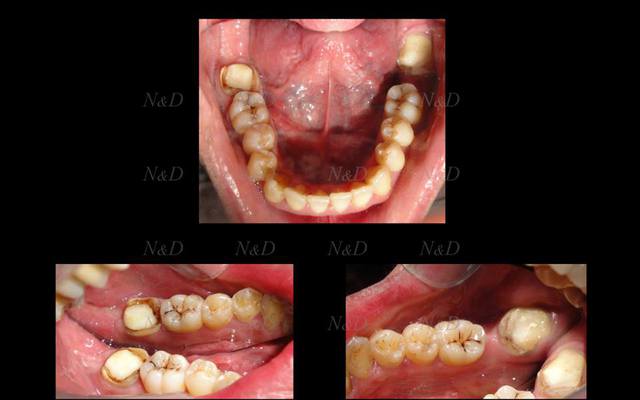

première tentative d'importation du .cdt

il y a apparemment enchevêtrement des différentes saisies et un pb de nettoyage qui n'est pas pris en compte comme il devrait à ce stade de la modélisation du .cdt.

L'empreinte optique vestibulaire de l'occlusion génère à mon avis les artefacts que l'on voit sous forme de "pics" dans le sens LV... Apparament pas de trace de la restauration finale. Je dois faire plus de tests et je repasse ici d'ici quelques temps ...